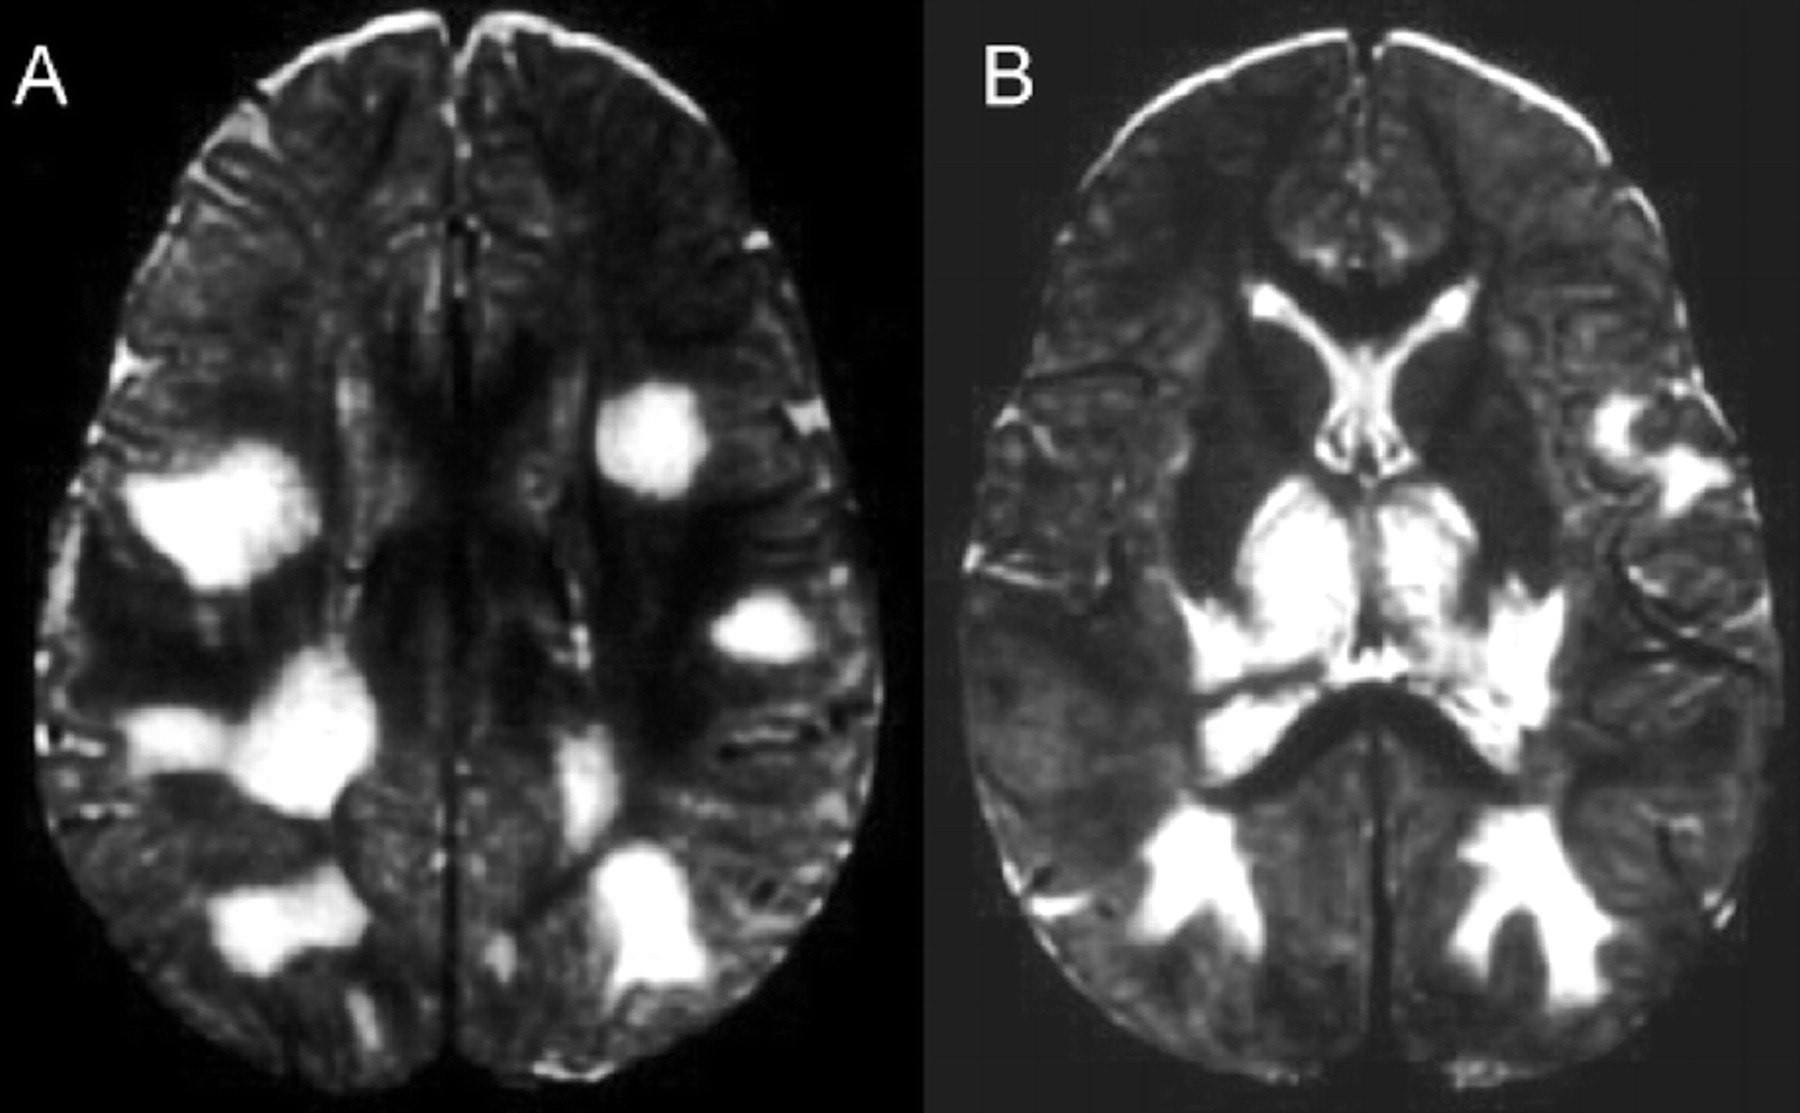

提出了四种模式的大脑参与描述ADEM的磁共振成像结果21:1)ADEM小病变(少于5毫米;图1);2)ADEM大支流,块状病变,簇状或频繁广泛perilesional水肿和质量效应(图2);3)ADEM附加对称bithalamic参与(图3);和4)急性出血性脑脊髓炎(咳咳),当一些出血的证据可以确定大脱髓鞘病变(图4)。核磁共振成像模式似乎并不与任何特定的结果或残疾,作为大型儿童群体中观察到,21因为大多数病变往往解决后续成像研究。21日,32然而,这种分类可能是有用的在考虑的鉴别诊断ADEM和可能有助于识别那些孩子来说,初始ADEM-phenotype真的是第一个女士的表现。

AHL,嗯哼,ANHLE被认为是亚当的hyperacute子表单,并观察到2%的儿童群体。21病变MRI上往往是大型perilesional水肿和质量效应。56、57Diffusion-weighted成像披露限制扩散的区域影响的大脑区域最近出版,57,这一发现可能是由于急性血管炎,随后在AHL血管闭塞。